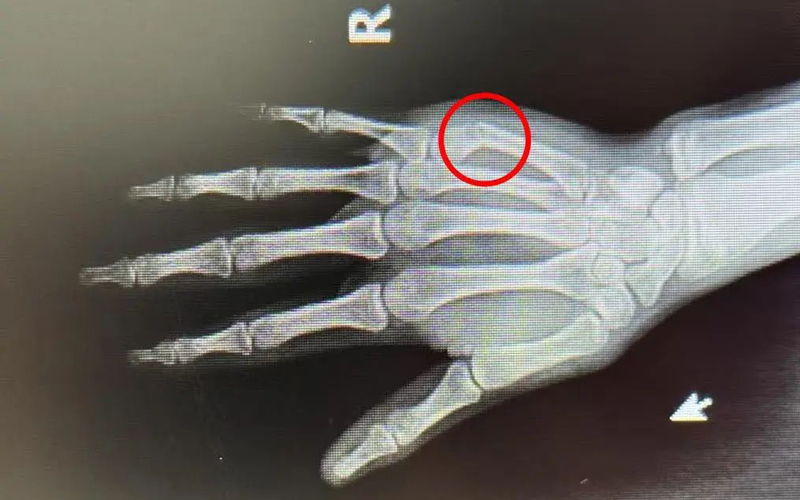

患者小徐今年16岁,因在学校不慎撞伤导致右手肿痛难忍来院就诊,穆中杰教授与科室医生认真研判病情,考虑患者为掌骨骨折可能,经过检查显示右手第5掌骨颈骨折,又称“拳击手骨折”,是临床上比较常见的手部骨折。

同患者及其家属进行沟通,决定行手法复位+杉树皮夹板固定,同时使用金黄散外用消肿止痛治疗,复位后骨折基本达解剖复位,患者及家属十分满意。

遂再次就诊于我院,经穆教授手法复位后,检查显示骨折复位良好。